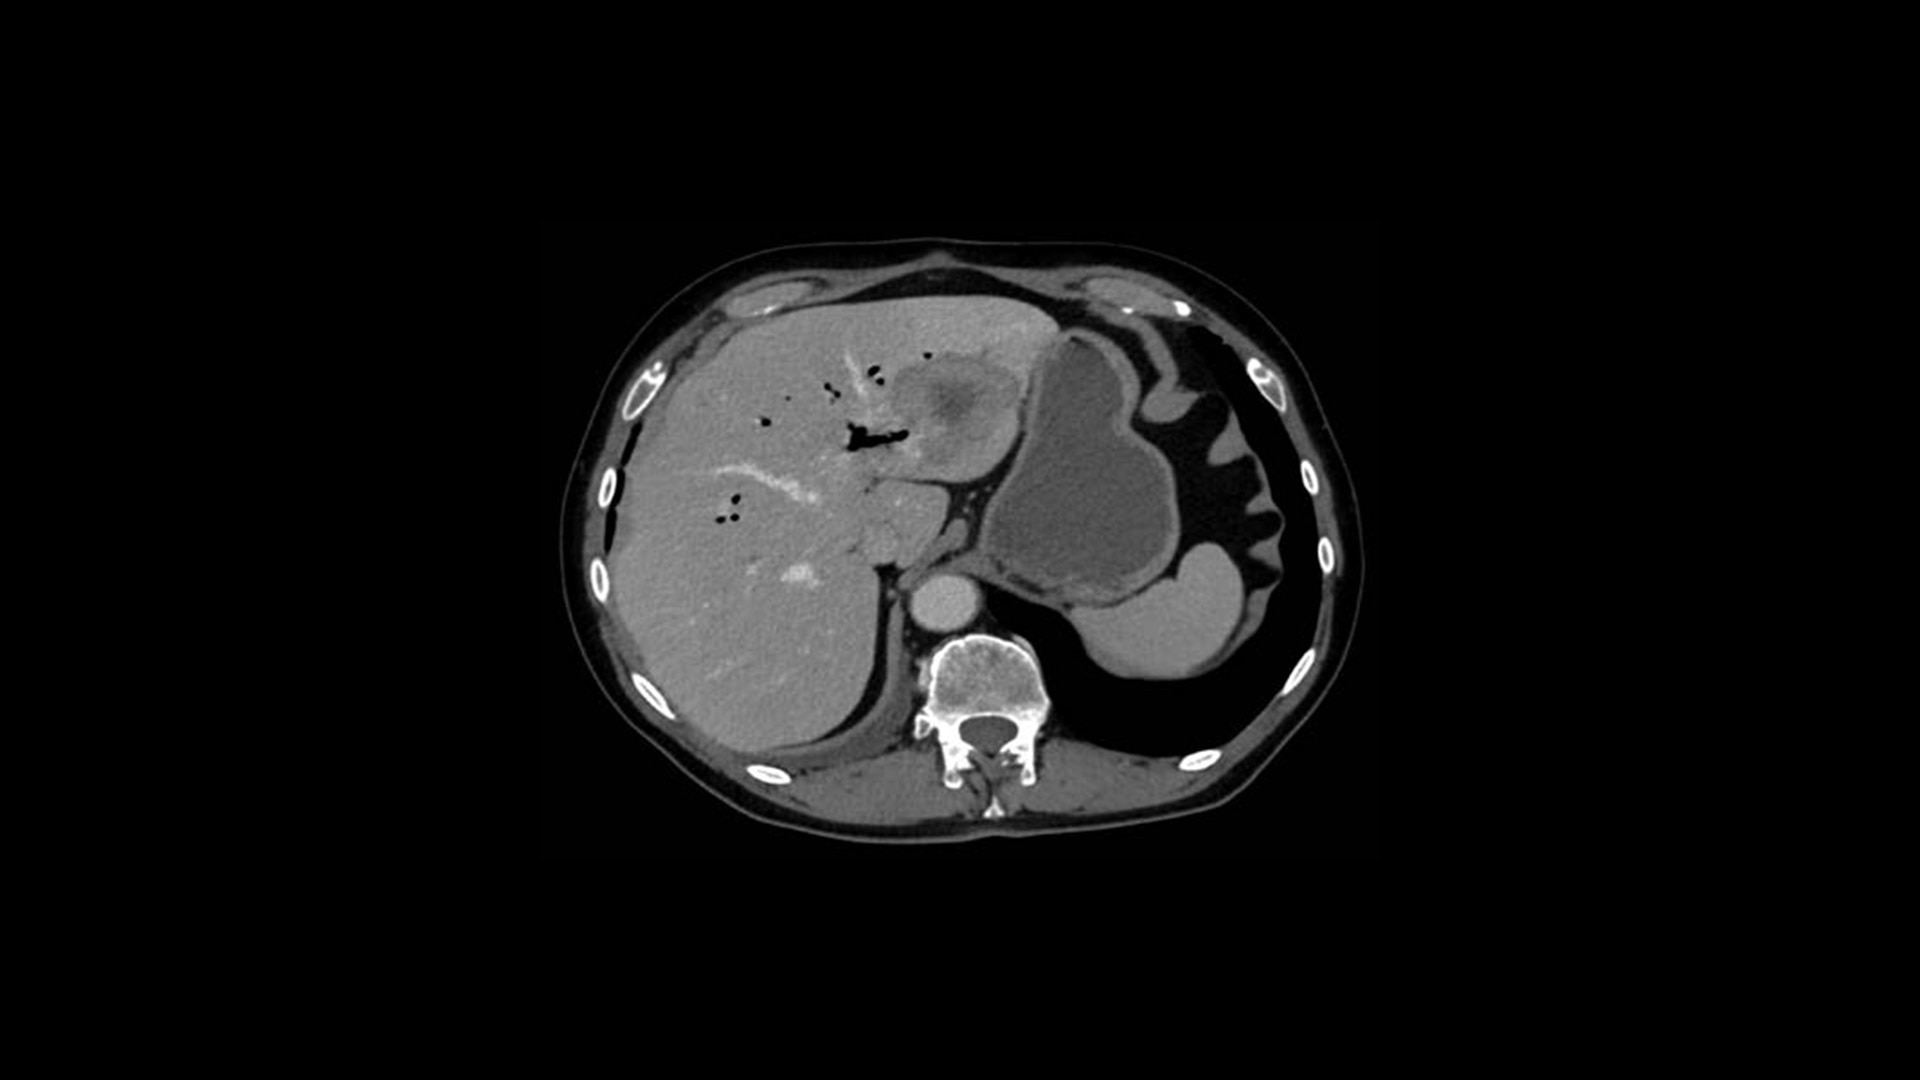

True Enhance DL is a deep learning-based processing method intended for contrast enhancement of single energy images. True Enhance DL uses a dedicated Deep Neural Network (DNN) trained to estimate monochromatic, 50 keV GSI images from single-energy X-ray. This technology brings four deep learning models that the user can choose depending on different contrast enhancement phases by clinical tasks.

TrueFidelity™ DL is our state-of-the-art image reconstruction technology that uses a DNN to generate high-definition, low-noise CT images. It produces images with exceptional sharpness, low-contrast image quality performance and your preferred noise texture, at the same dose.¹